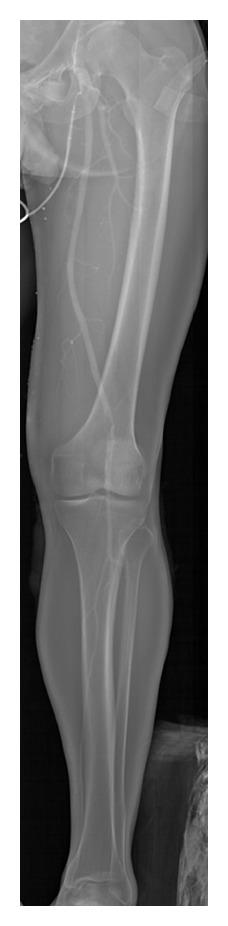

This paper reports on the application of full-body radiography to nontraumatic emergency situations. The Lodox Statscan is an X-ray machine capable of imaging the entire body in 13 seconds using linear slit scanning radiography (LSSR). Nontraumatic emergency applications in ventriculoperitoneal (VP) shunt visualisation, emergency room arteriography (ERA), detection of foreign bodies, and paediatric emergency imaging are presented. Reports show that the fast, full-body, and low-dose scanning capabilities of the Lodox system make it well suited to these applications, with the same or better image quality, faster processing times, and lower dose to patients. In particular, the large format scans allowing visualisation of a greater area of anatomy make it well suited to VP shunt monitoring, ERA, and the detection of foreign bodies. Whilst more studies are required, it can be concluded that the Lodox Statscan has the potential for widespread use in these and other nontraumatic emergency radiology applications.

本文报道了全身X线摄影在非创伤性紧急情况中的应用。Lodox Statscan是一台X线机,能够使用线性狭缝扫描摄影(LSSR)在13秒内对全身进行成像。介绍了其在脑室腹腔(VP)分流可视化、急诊室动脉造影(ERA)、异物检测和儿科急诊成像等非创伤性紧急情况中的应用。报告显示,Lodox系统快速、全身和低剂量的扫描能力使其非常适合这些应用,具有相同或更好的图像质量、更快的处理时间以及更低的患者辐射剂量。特别是大幅面扫描能够显示更大范围的解剖结构,使其非常适合VP分流监测、ERA和异物检测。虽然还需要更多研究,但可以得出结论,Lodox Statscan在这些及其他非创伤性紧急放射学应用中有广泛应用的潜力。